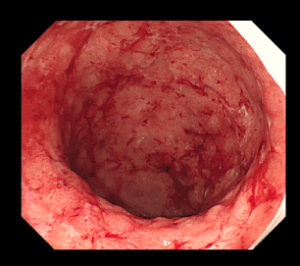

潰瘍性大腸炎の大腸カメラ像

大腸がひどくただれて血がにじんでいます。1日に10回近い粘血便、下痢を主訴に受診されました。5-ASA製剤というお薬を内服して症状は改善しました。